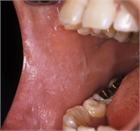

1. 口腔の粘膜疾患は口腔粘膜に症状を呈する病変の総称であり、その中にはさまざまな病変が含まれる。口腔粘膜に限局した疾患、顎顔面領域における病変が波及して口腔粘膜症状を呈したり、自己免疫疾患、内科疾患、皮膚疾患の部分症状が口腔粘膜に出現することもある。口腔粘膜に発現した疾患の鑑別診断により、全身性疾患が発見されることを加筆した。

1. 口腔の粘膜疾患は口腔粘膜に症状を呈する病変の総称である。

1. 口腔の粘膜疾患は口腔粘膜に限局して発現する病変のほかに、内科疾患、自己免疫疾患、皮膚疾患などの部分症状として口腔粘膜に病変が出現するものがある。